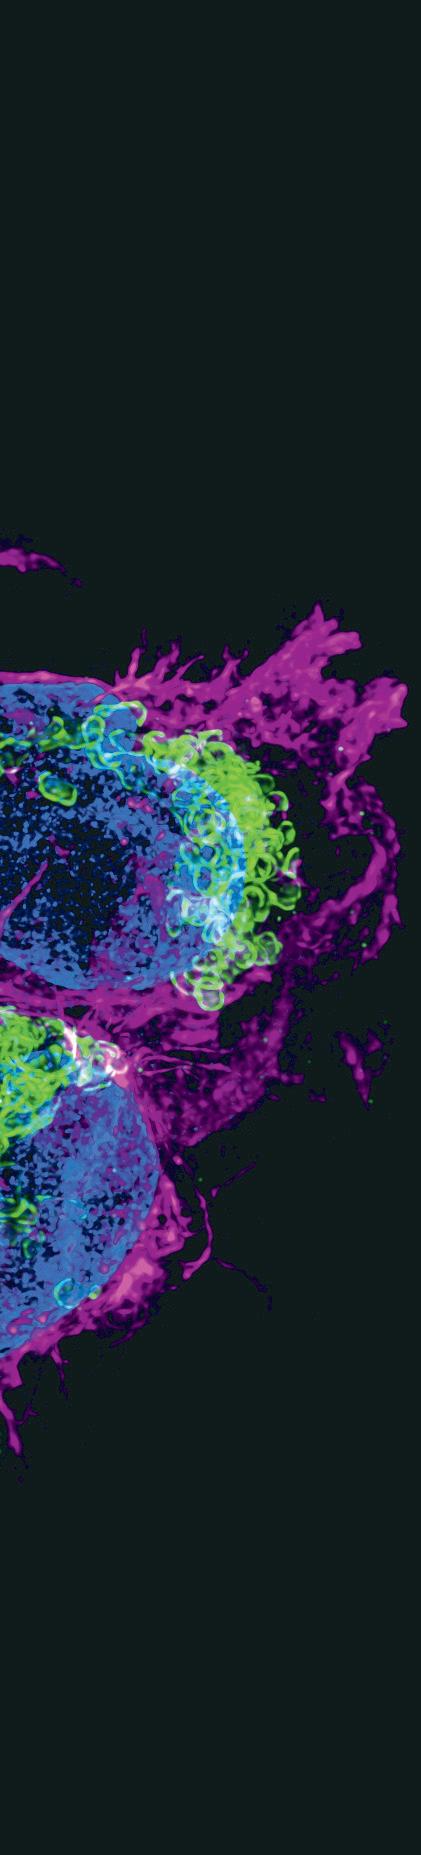

Fotografie na obálce: „Cellular harmony: The Interplay of action, mitochondria and the nucleus in B cells“. Vítězný mikrosnímek soutěže CELLIM Best Microscopy, Picture Contest 2024, autorem je Narenda Varma Gottumukkala, Masarykova univerzita, CEITEC, výzkumná skupina Michala Šmídy.